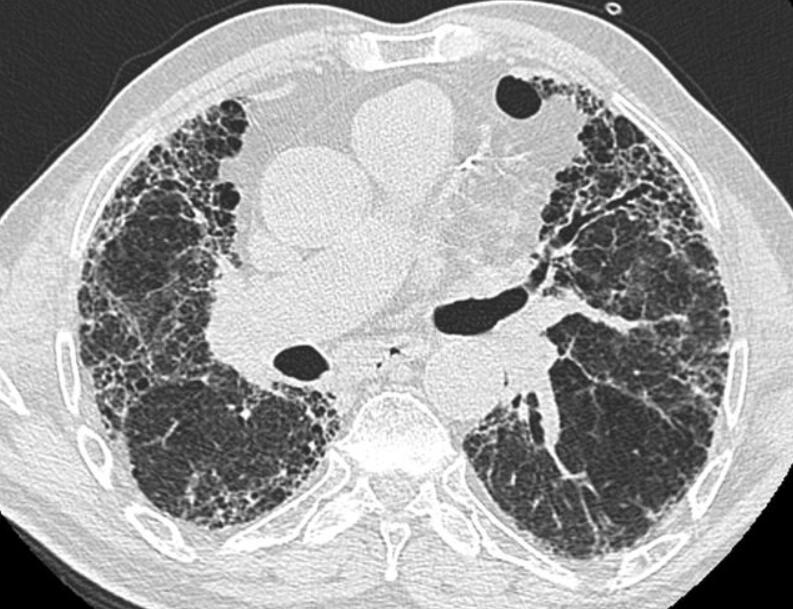

2023年10月24日,Bristol Myers Squibb(NYSE:BMY)宣布美国食品和药物管理局(FDA)已为BMS-986278授予突破性疗法认定,这是一种潜在的首创性口服药物,为进展性肺纤维化(PPF)的治疗提供新途径。进展性肺纤维化是一种具有毁灭性和威胁生命的疾病,目前只有一种治疗方法被批准用于其治疗。本文将深入探讨这一好消息,分析BMS-986278的突破性潜力以及它对肺纤维化患者的重大影响。

获得FDA的突破性疗法认定是基于全球范围内进行的随机分组的2期研究结果,该研究评估了BMS-986278治疗与安慰剂在特发性肺纤维化(IPF)和PPF患者中的安全性和疗效。在IPF队列中,允许稳定的抗纤维化药物背景治疗,而在PPF队列中则可以选择性使用免疫抑制药物。PPF队列的结果显示,采用每日60毫克两次的BMS-986278治疗26周,与安慰剂相比,呼吸功能的百分比预测强制肺活量下降速度相对减少了69%。无论是否伴随背景治疗,BMS-986278的治疗效果都相当一致,而且耐受性良好,不良事件发生率类似于安慰剂,且停药率低。这些研究结果于2023年9月在欧洲呼吸学会(ERS)2023国际大会上进行了发布。

肺纤维化患者经历肺功能的不断下降,呼吸症状的恶化以及生活质量的降低,最终可能导致呼吸衰竭和死亡。Bristol Myers Squibb的高级副总裁兼免疫学、心血管和神经科学开发部门负责人Roland Chen博士表示:“患有肺纤维化的患者面临着肺功能的不断恶化,呼吸症状的恶化以及生活质量的降低,最终可能导致呼吸衰竭和死亡。” “FDA的突破性疗法认定强调了BMS-986278作为一种创新的首创性治疗的潜力,它可能重新定义进展性肺纤维化的标准治疗。”